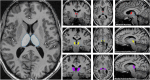

Figures